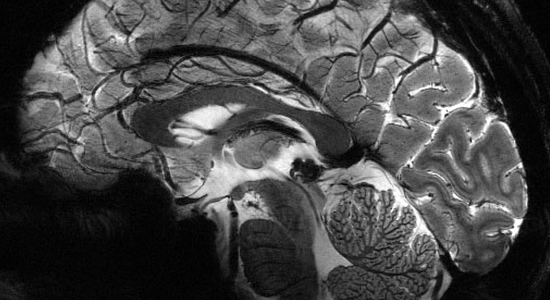

Le Cerveau Amoureux

Difficile de définir ce qu'est l'amour ! Nous pouvons cependant, en tant que neurobiologistes, avancer son rôle fondamental pour l'Homme. En effet le cerveau a mis en place des systèmes garants de la perpétuation et l'évolution de l'espèce humaine. Que ce soit au niveau de l'individu ou de la société, quels rôles spécifiques jouent ces systèmes ? Quels sont les mécanismes neurobiologiques (neurochimiques) qui les sous-tendent ? Sont-ils toujours bénéfiques et pour qui ? Que se passe-t-il dans le cas de dysfonctionnements ? Enfin l'amour est-il une création purement humaine ou bien est-il exprimé aussi par les animaux ? Ces questions ont pour certaines des réponses multiples comme le sont les formes de l'amour.